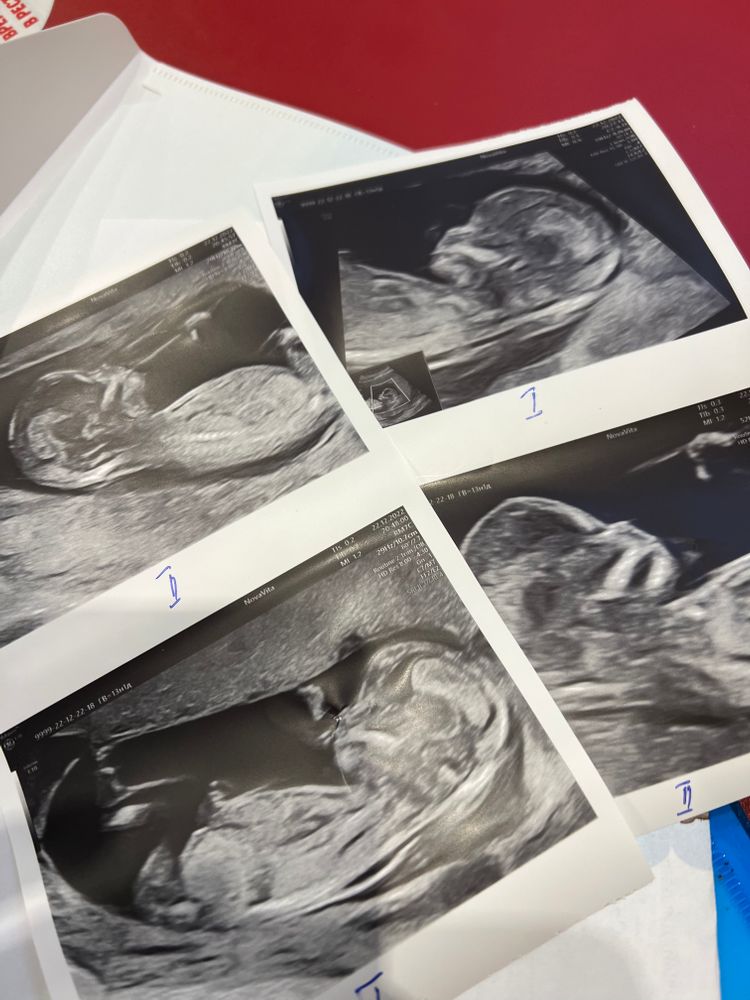

Первый скрининг, двойняшки

Изображение

Привет девочки! Как время быстро летит, уже 13/14 недель моим двойняшкам. 22 декабря проходила первый скрининг! Такие большие уже человеки, с ума сойти!